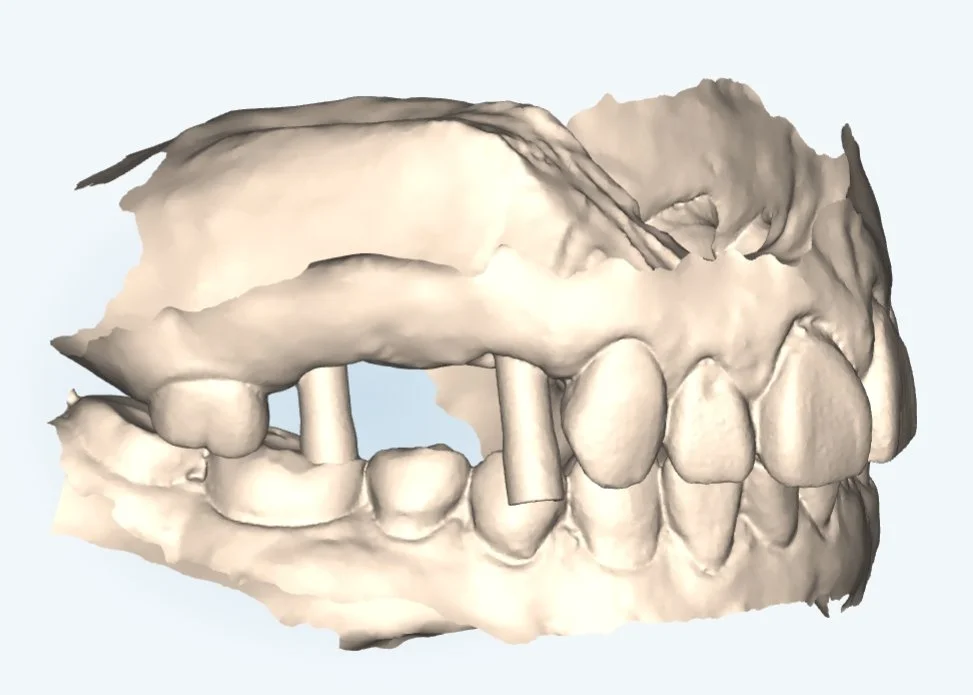

Advantages of Digital Dentistry

With precise 3D scans and CAD/CAM-designed prosthetics, treatments fit perfectly the first time—reducing remakes and speeding up patient care.

Digital workflows streamline production, meaning your restorations are delivered more quickly without sacrificing quality.

Streamlined Workflow & Consistent Quality Errors

Our digital processes replace traditional manual steps, helping to minimize mistakes and save time in both treatment planning and prosthetic fabrication, while precision technology ensures high-quality, predictable restorations.